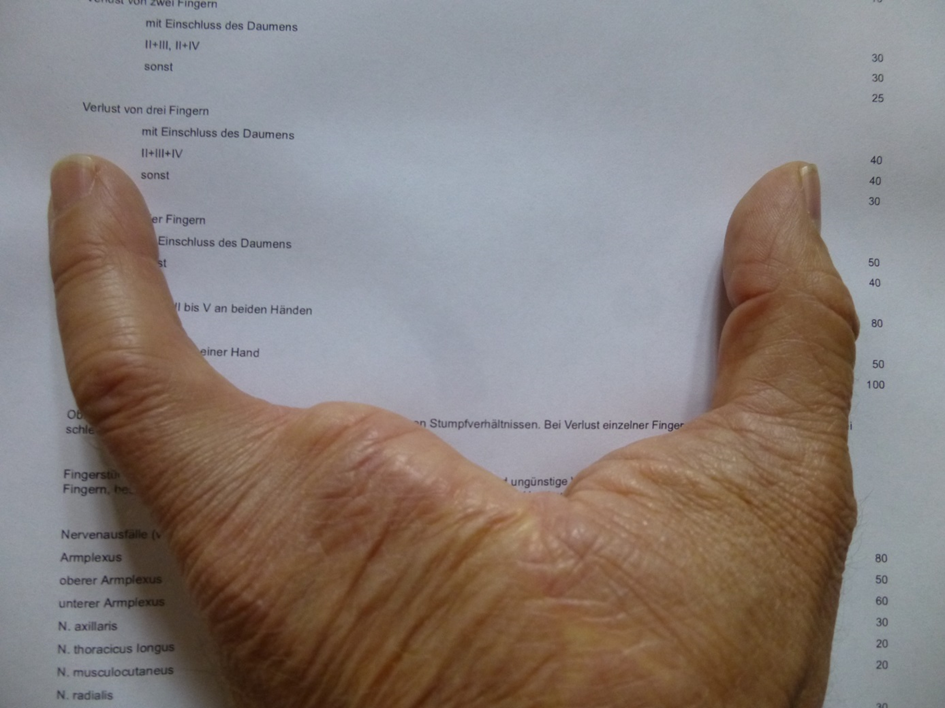

Das Foto zeigt die linke Hand sowie einen Auszug aus der VersMedV (Versorgungsmedizinverordnung)

Es fehlen die Finger II+III+IV sowie ein Teil der Mittelhand

In der VersMedV ist dafür ein GdB von 40 festgelegt

Das Versorgungsamt hat einen GdB von 30 zugesprochen.

Damit ist bewiesen, dass das Versorgungsamt eine deutlich zu niedrige Bewertung gegen geltendes Recht zu Ungunsten meiner Person vorgenommen hat.

Der Unrechtstatbestand besteht seit 1983 und wurde erst 2015 korrigiert, nachdem ich wiederholt auf den Fehler hingewiesen habe.

Einen Ausgleich für den damit verbundenen wirtschaftlichen Schaden (>5000€) hat es nicht gegeben.